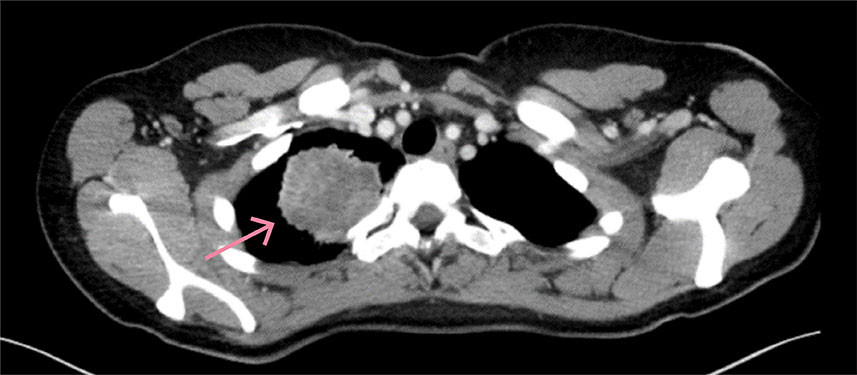

Pasienten var etter utskrivelse i psykisk bedring og gjenvant normalvekt. Etter initial systemisk behandling, som også inkluderte karboplatin og bevacizumab, mottok hun intravenøst pembrolizumab og pemetreksed hver tredje uke i totalt to år. Til å begynne med husket hun lite av det hun hadde gjennomgått. Hun har i ettertid uttrykt behov for å bearbeide og forstå det hun har vært gjennom, og minnene har gradvis dukket opp som «flashbacks». Prognose har vært et tema ved flere konsultasjoner, der pasienten spør om hun er frisk. Vi har svart henne at når hun fire år etter symptomdebut og to år etter behandlingspause ikke har tegn til residiv, gir det håp om langvarig effekt. Billedmessig har hun kun små restforandringer (figur 3). Pasienten bor nå i egen leilighet med barnet sitt, er arbeidssøkende og i funksjonsklasse 0 (ingen begrensninger i dagliglivet).